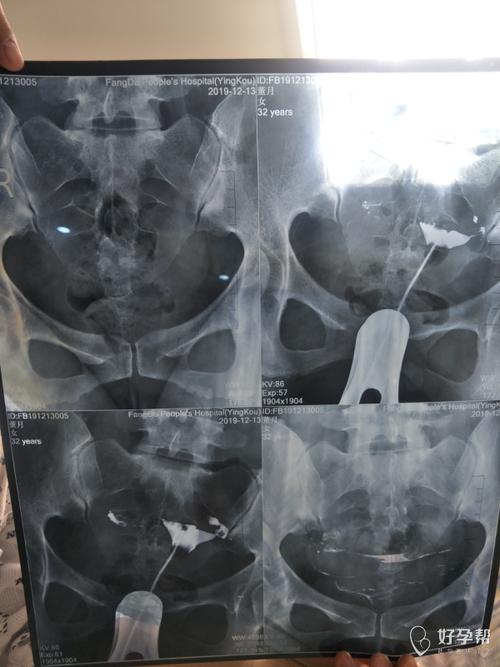

输卵管疏通手术,包括通液通术和子宫输卵管造影手术。输卵管不通的患者需要在生五天到九十天内,排精,正常工作和活动要禁下禁动。如果有什么异常,要做介入手术。

输卵管手术(通液、疏通、或经手术)一般在月经来潮5天以后,6小时前不可以做输卵管的插管和造影。输卵管结扎后需要休息2周左右,并且禁止盆浴、盆浴。